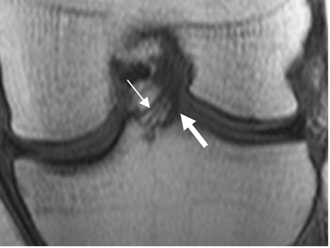

Fig 30. Meniscos normales.

A: RM coronal en STIR. Menisco interno (Flecha delgada) y menisco externo (Flecha gruesa). B: RM axial en T2. Menisco interno (Flechas delgadas) y Externo (Flechas gruesas).